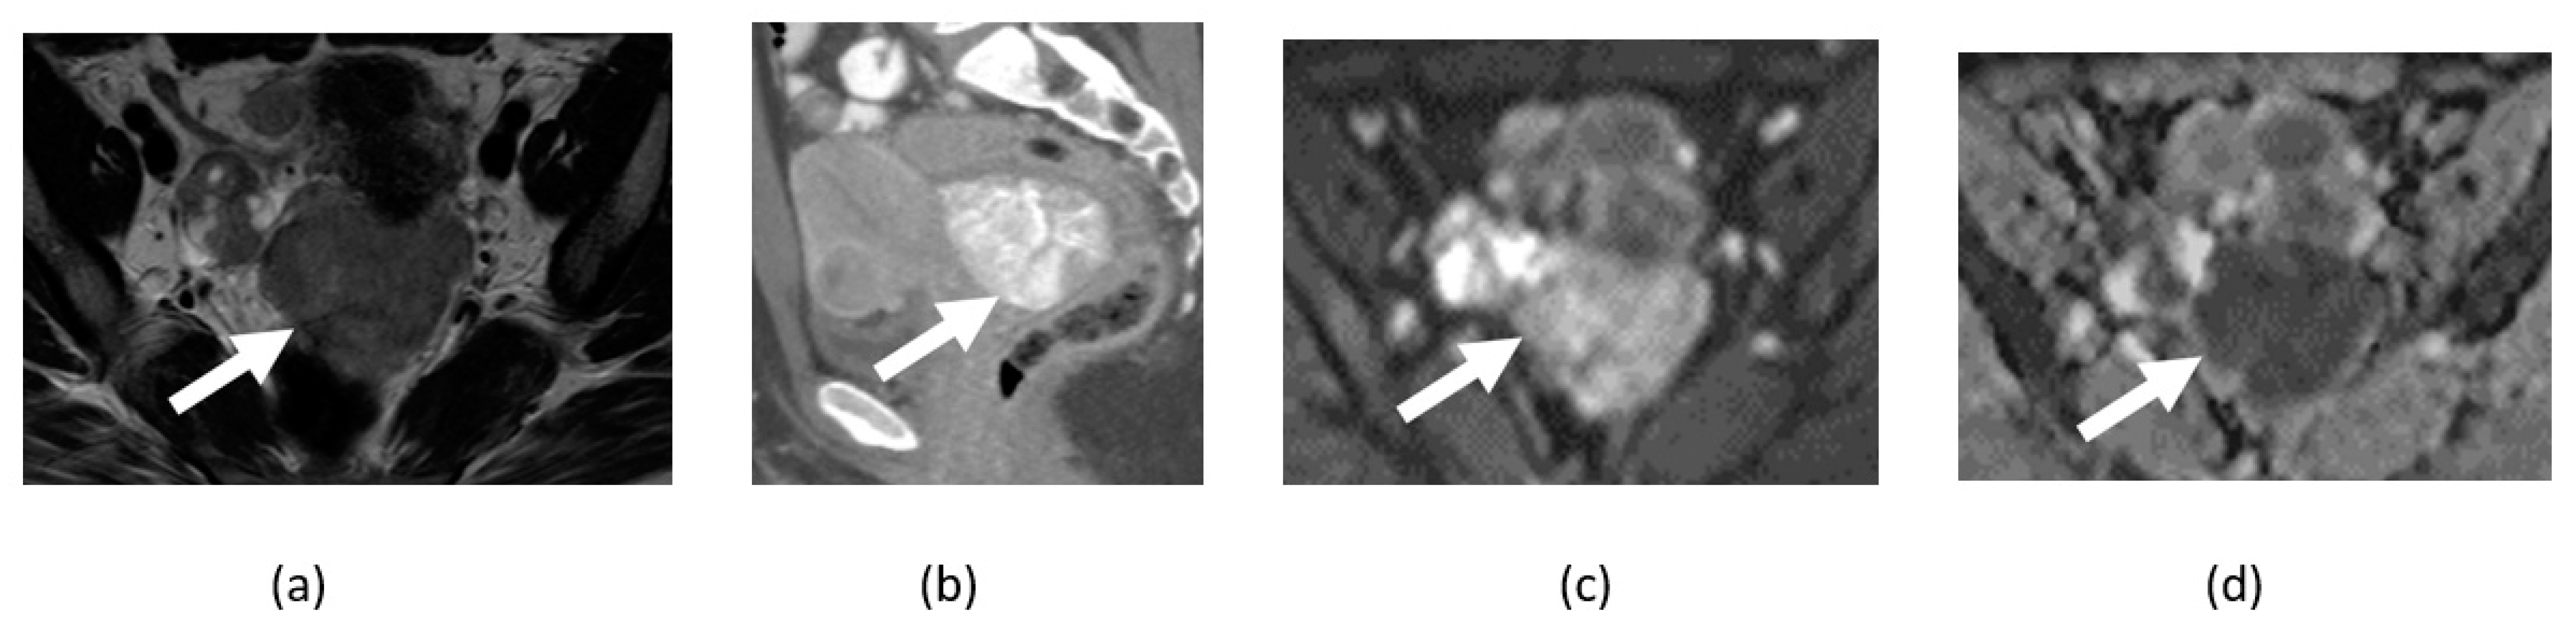

4.3. Ovarian Cancer